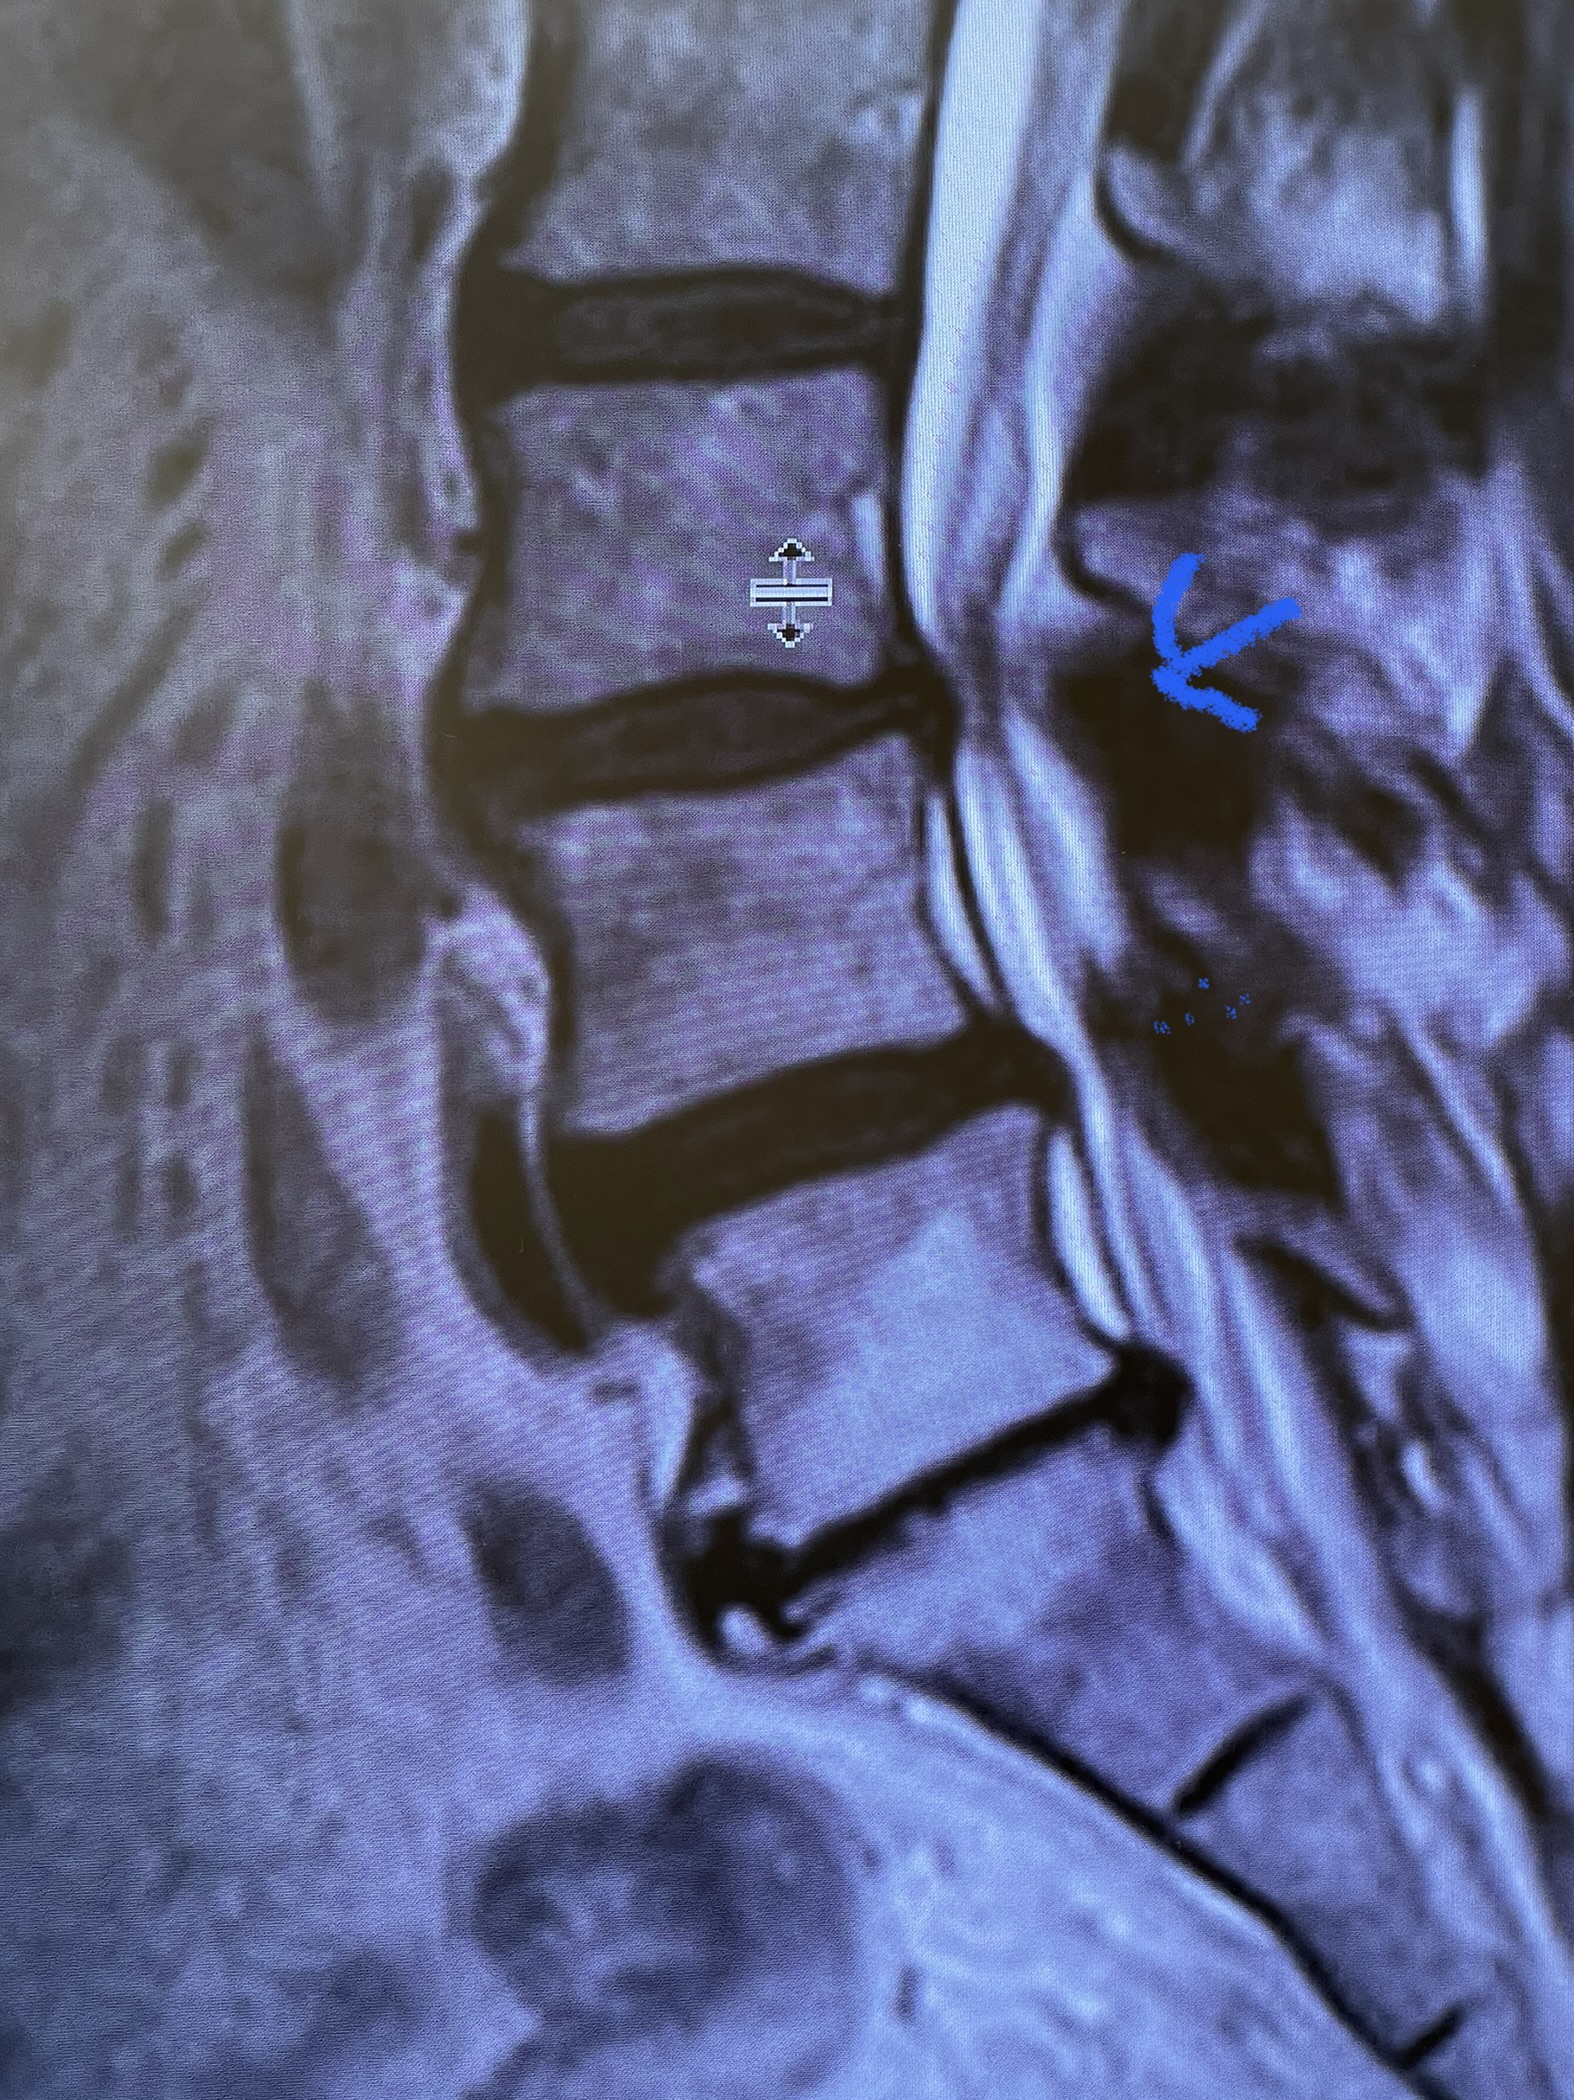

Figure 1. The sagittal MRIs demonstrate a very tight stenosis at T10-11 (blue arrow). Note the area of hyperintensity within the spinal cord at this level representing myelomalacia (red dot). Patient also has significant stenosis at T11-12 (purple arrow).

This 50-year-old morbidly obese female presents with one month of progressive weakness of her lower extremities. She also reported numbness and pain in her thighs. Her right leg was worse, and she had one episode of urinary incontinence. She had some back pain. She was ⅖ strength in her right hip flexor and quadriceps. She was ⅘ in her left lower extremity. MRI (Figure 1 and Figure 2) revealed very tight stenosis circumferentially at T10-11 secondary to facet hypertrophy and anterior disc osteophyte complex with associated myelomalacia of the spinal cord. There was also stenosis to a lesser degree but still significant at the T11-12 level.